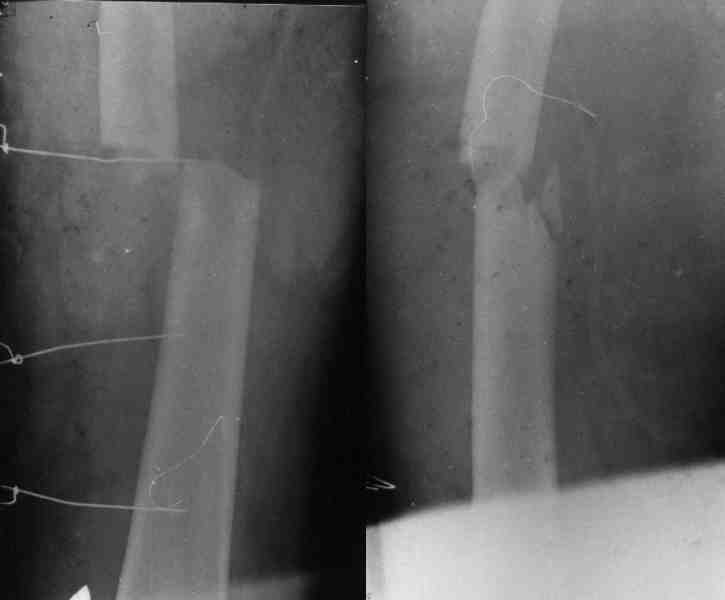

Уважаемый Михаил Викторович! У нас имеется небольшой опыт блокируемых остеосинтезов плечевой кости (20-30), однако был печальный случай (у пациента, в другой клинике, плечо было оперировано гвоздем Кюнчера!!! - произошло отвисание дист фрагмента) , Нами был ваполнен БИОС (проксимальное блокирование одним винтом), через месяц произошло прорезывание порозной кости и погружение винта под кортикал с образованием диастаза между фрагментами, пришлось найти и извлечь этот винт, немного выбить стержень (не

вскрывая место перелома и не убитрая дистальные блокирующие винты) и выполнить проксимальное блокирование двумя винтами.

Так. как вы планируете пациенту повторное вмешательство - может быть удалить прокс. блок. винт забить гвоздь на 10- мм. и сделать блокирование двумя винтами?